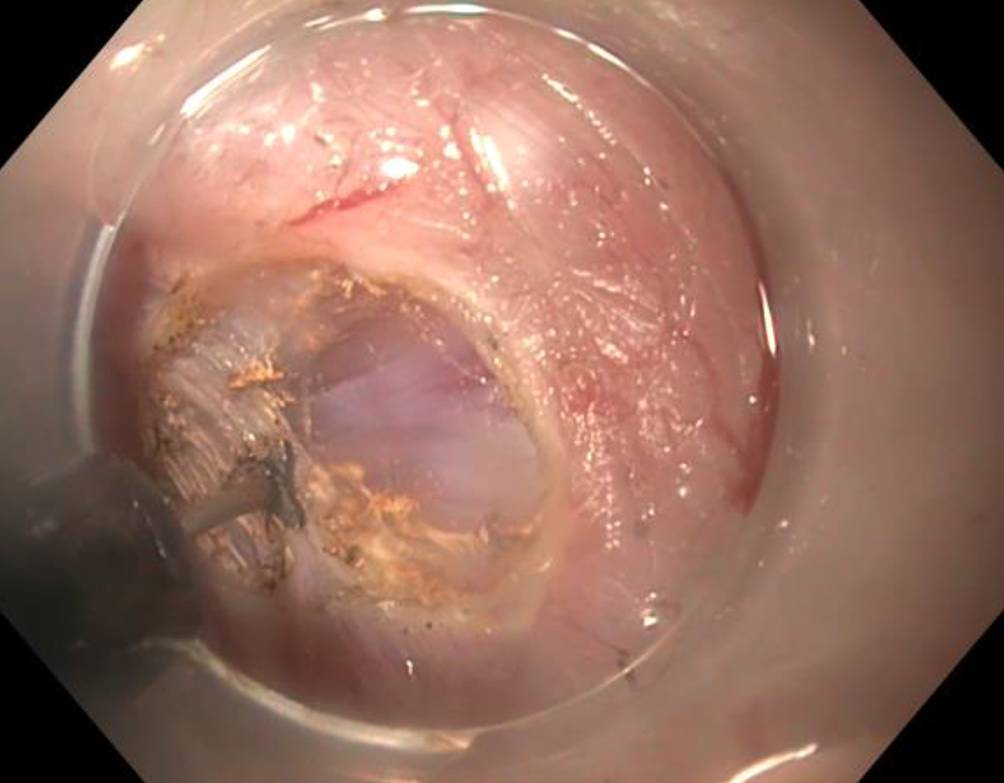

Wir führen POEM in Intubationsnarkose und mit CO2-Insufflation durch. Nach submuköser Injektion wird die Mukosa ca. 12 cm oberhalb der Kardia inzidiert und ein submuköser Tunnel über die Kardia hinweg bis in den proximalen Magen präpariert. Dann wird die innere Ringmuskulatur von 2 cm distal der Kardia nach proximal bis ca. 3 cm unterhalb der Mukosainzision durchtrennt, die Längsmuskulatur wird erhalten. Abschließend wird der Tunneleingang mit Clips verschlossen (Abb. 1, 2 und 3).

Abb. 1

Myotomie während POEM

Abb. 2

Myotomie während POEM: Durchtrennung der Ringmuskulatur, Erhalt der Längsmuskulatur